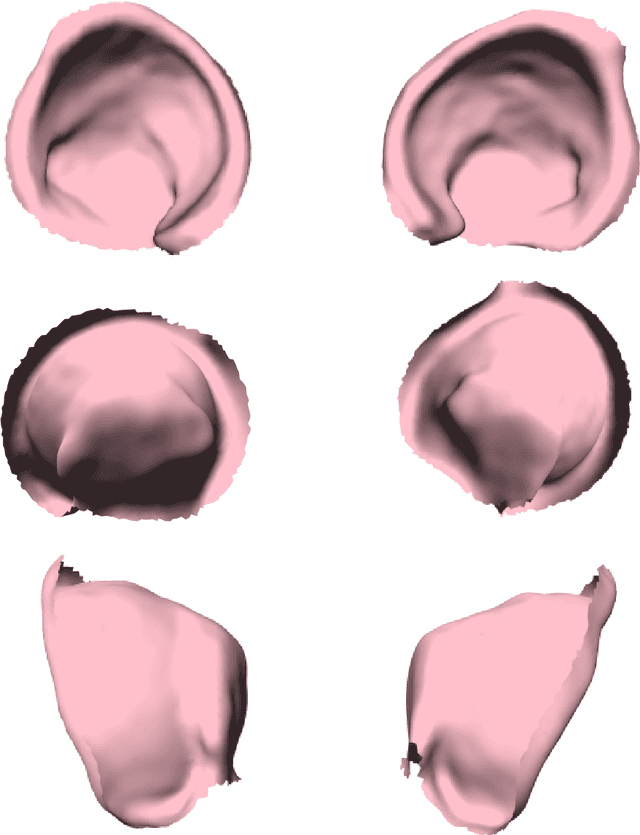

Abstract:Dysplasia is a recognised risk factor for osteoarthritis (OA) of the hip, early diagnosis of dysplasia is important to provide opportunities for surgical interventions aimed at reducing the risk of hip OA. We have developed a pipeline for semi-automated classification of dysplasia using volumetric CT scans of patients' hips and a minimal set of clinically annotated landmarks, combining the framework of the Gaussian Process Latent Variable Model with diffeomorphism to create a statistical shape model, which we termed the Gaussian Process Diffeomorphic Statistical Shape Model (GPDSSM). We used 192 CT scans, 100 for model training and 92 for testing. The GPDSSM effectively distinguishes dysplastic samples from controls while also highlighting regions of the underlying surface that show dysplastic variations. As well as improving classification accuracy compared to angle-based methods (AUC 96.2% vs 91.2%), the GPDSSM can save time for clinicians by removing the need to manually measure angles and interpreting 2D scans for possible markers of dysplasia.